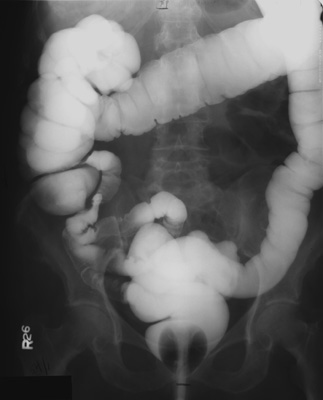

- PA view of colon to include rectum -

patient prone, perpendicular central ray, 14" x 17" cassette